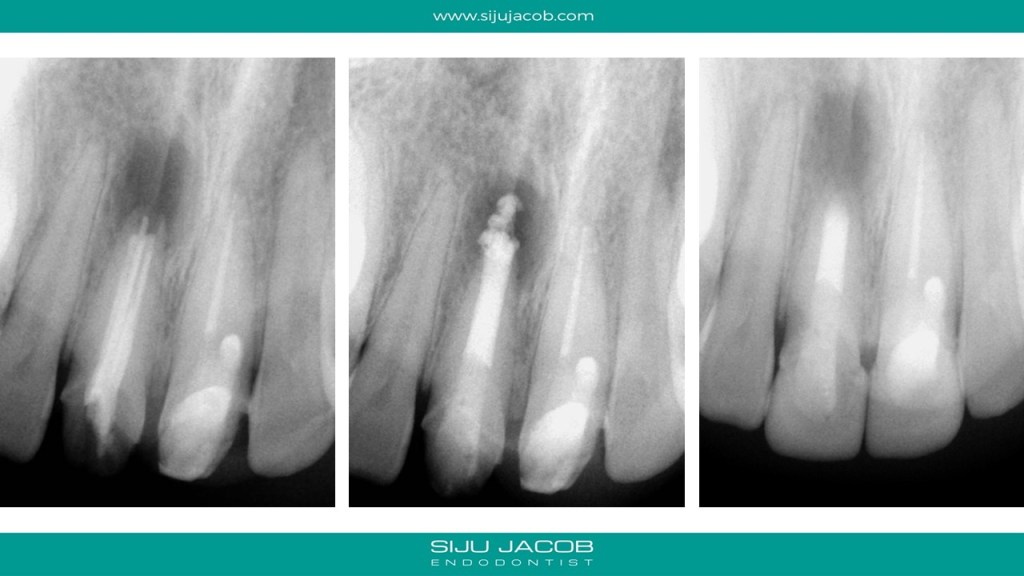

This was a patient who traveled from abroad from Treatment. We had only 9 days to do his treatment. So, we did endo and immediate surgery.